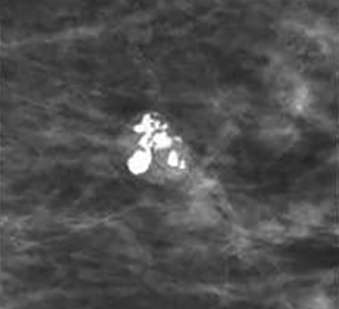

Coarse Heterogeneous Calcifications

Coarse heterogeneous calcifications: irregular and defined calcifications which often coalesce, coarse heterogeneous calcifications usually measure more than 0.5 mm but less than the dystrophic calcifications. One lone group of coarse heterogeneous calcifications is considered a 4B category finding.